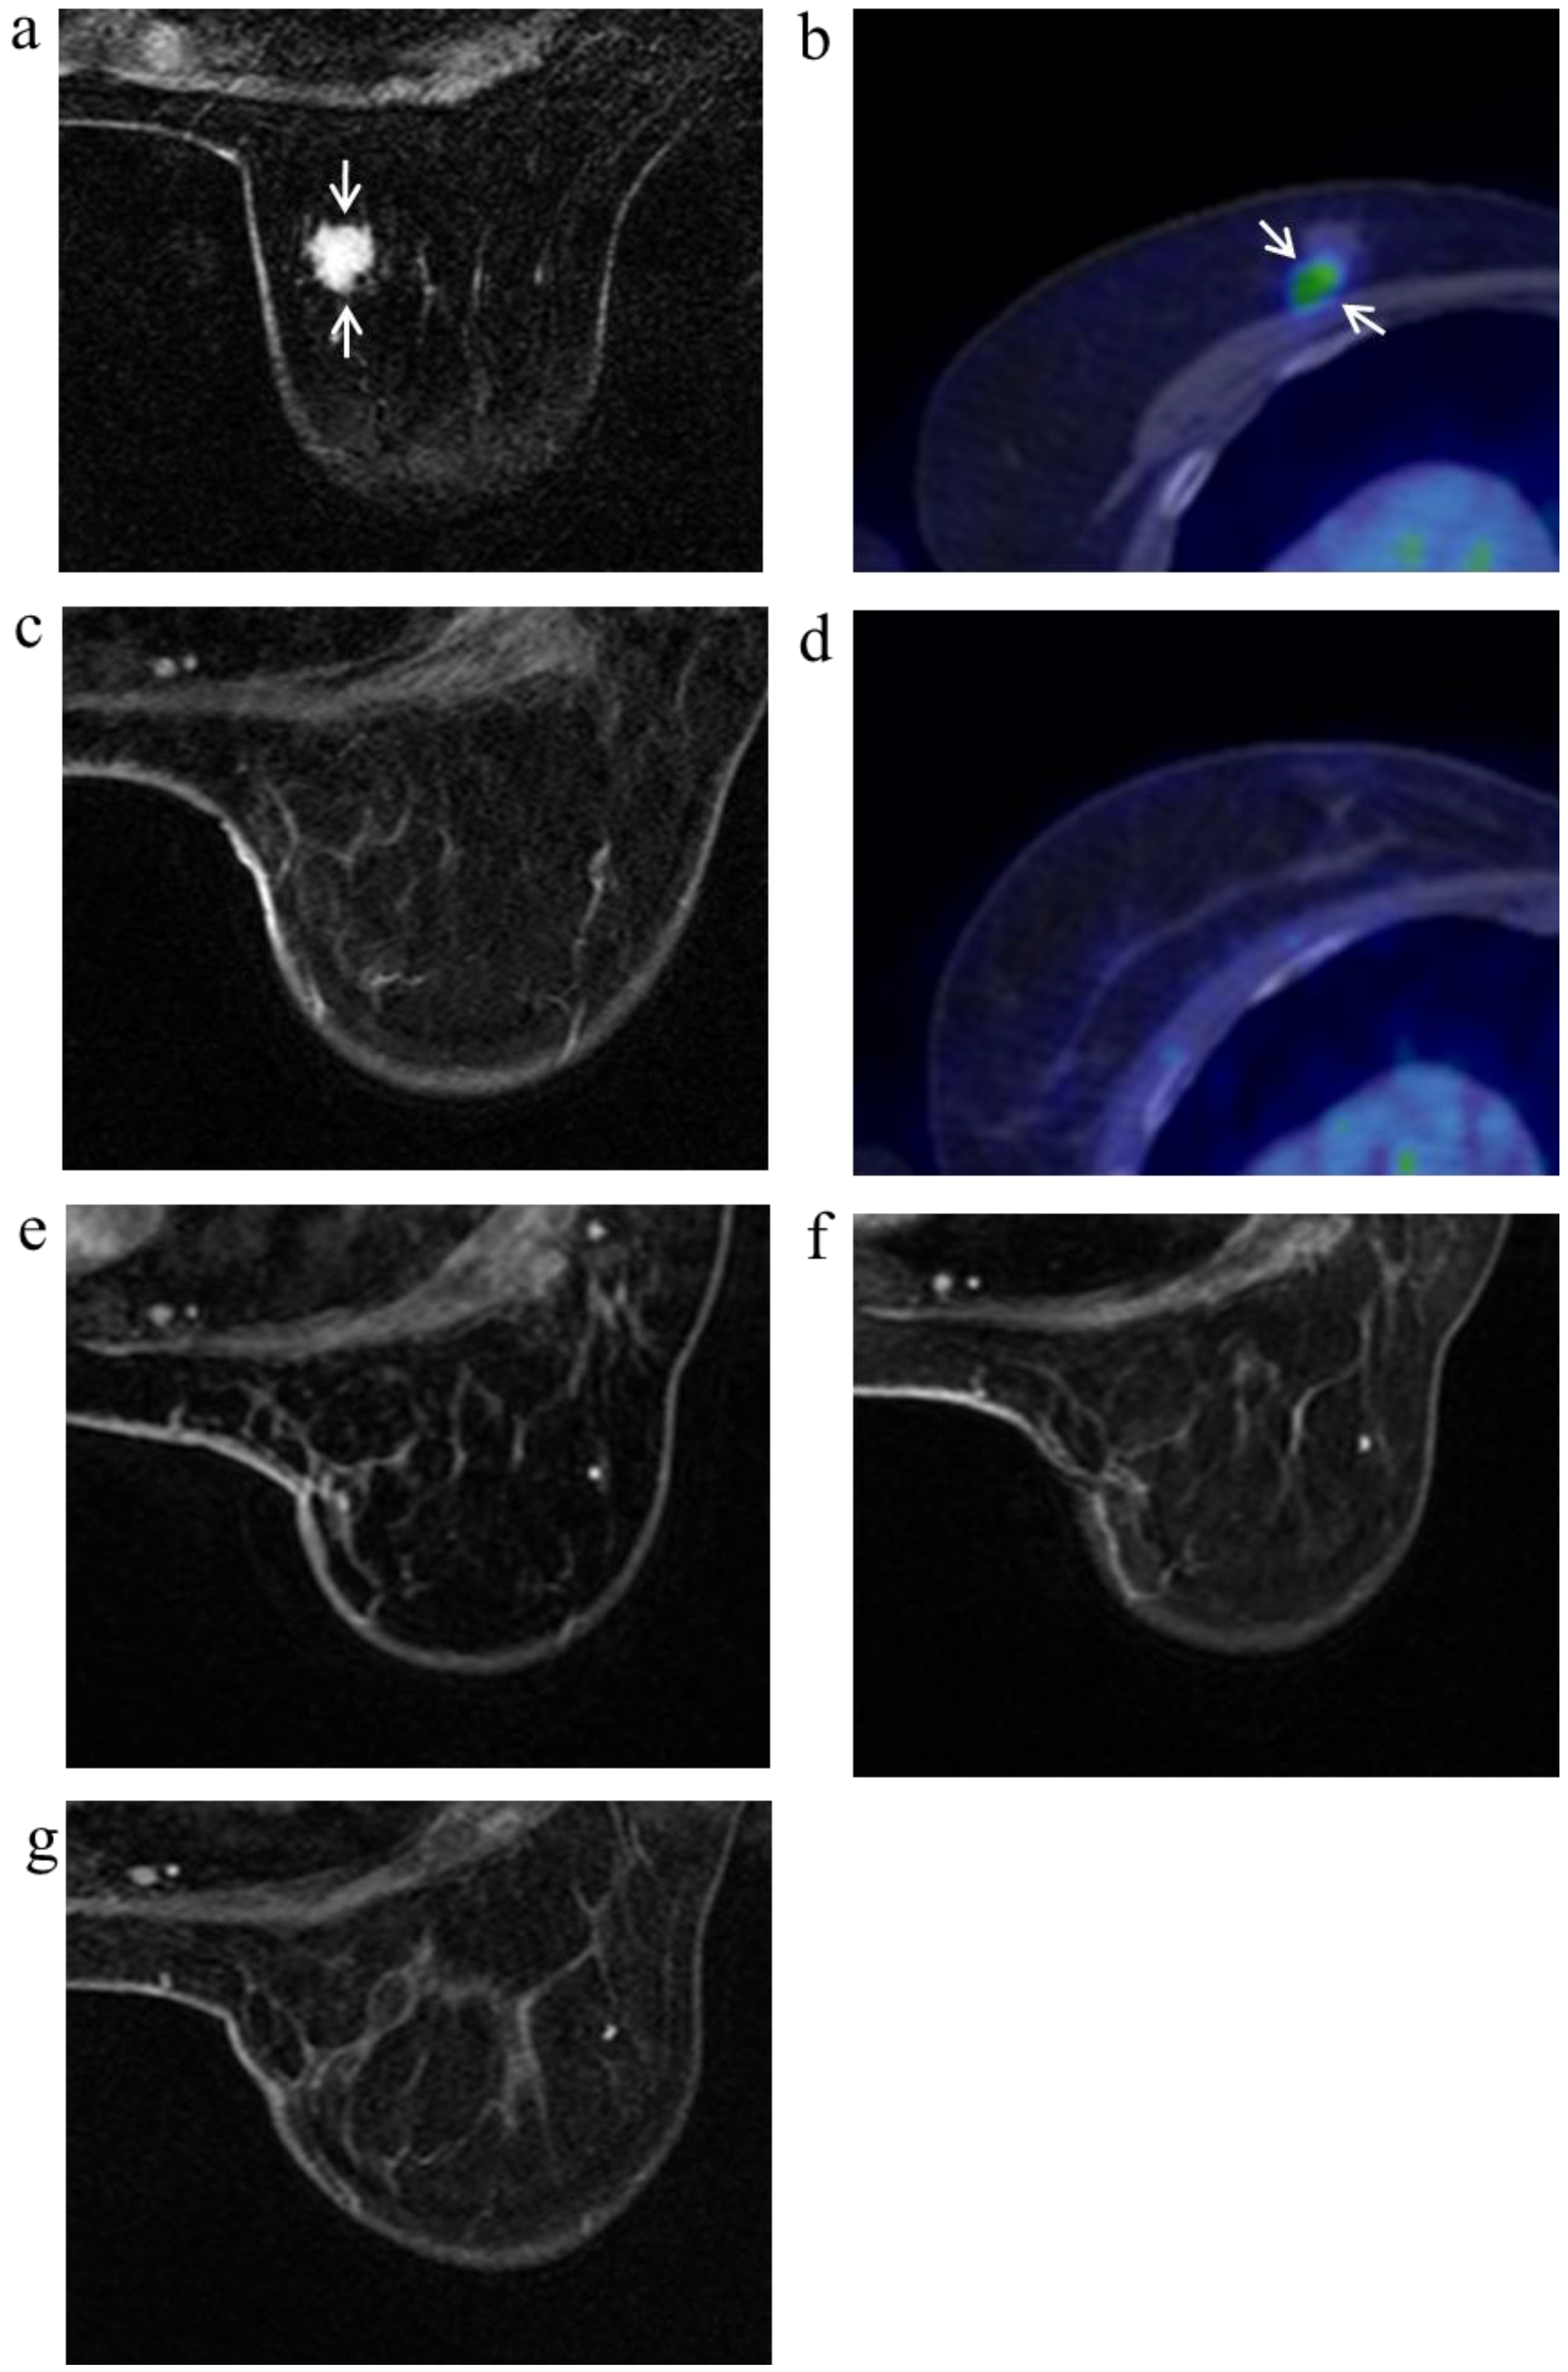

Figure 4.

A 63-year-old female (case 8 in Table 1, Table 2 and Table 3) with right breast cancer (cT1cN0M0). CE breast MRI (a) and FDG-PET-CT (b) revealed a breast tumor before KORTUC II therapy (arrows), the region of tumor was 13 mm; After KORTUC II, no recurrence was identified on CE breast MRI and FDG-PET-CT ((c): 10 months; (d): 18 months; (e): 22 months; (f): 34 months; (g): 50 months).